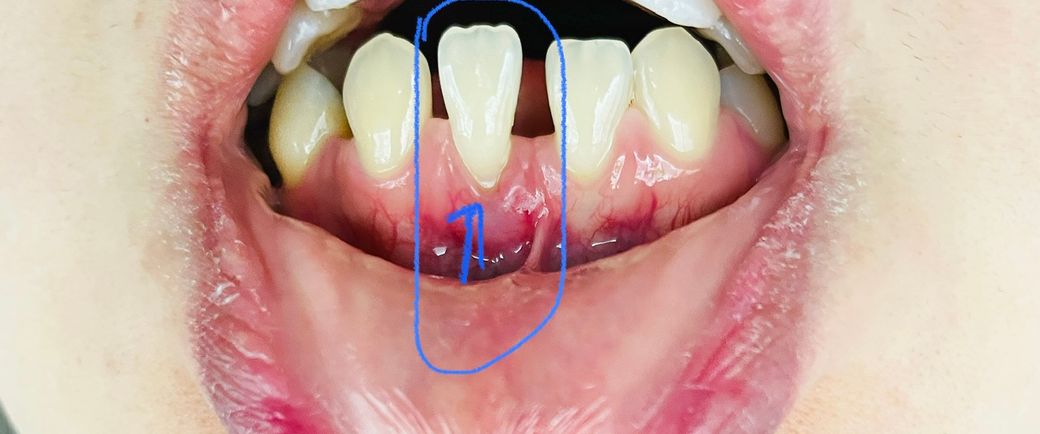

잇몸 염증 문의 드립니다 잇몸이 패여 내려가고 있어요

사진 첨부한 부분은 앞쪽 아랫니 한개 입니다

그러다가 며칠전부터는 저 치아 아랫부분

잇몸도 패이면서 내려가고 있어요

치아가 패인게 아니고 잇몸이 내려가고 있고 시린 증상이요 ㅠ 저 치아주위로 염증도 유지되구요

• 1번 째 사진

현재 정도는 잇몸이 많이 내려간 것도 파인 부위가 심한 것도 아닙니다. 하지만 불편감이 있다면 예방적으로 해당 부위를 수복해볼 수는 있습니다. 지금으로서는 스케일링을 다시 하시고 2주 뒤에 잇몸 치료를 한 번 받아보시길 바랍니다. 보통 잇몸치료를 하더라도 스케일링부터 시작하게 되며 잇몸 위에 있는 치석을 제거하고 잇몸 아래 제거를 많이 합니다.

잇몸이 내려간경우에는 자연적으로 재생이 되지 않습니다. 저 부분만 잇몸이 내려가셧다면 교합이 좋지 않거나 그쪽부위를 양치를 너무 강하게 하는게 아닐까 생각됩니다 시리시다면 레진으로 떼우시면되지만 증상이 없다면 양치만 잘하시면 크게 문제가 되진 않을것같습니다.